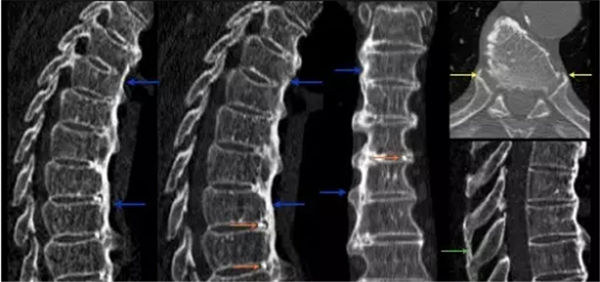

“弥漫性特发性骨质增生症”,一听这名字,就有种“不明觉厉”的感觉。弥漫性特发性骨质增生症多见于老年人,是影像学检查发现的一种以脊椎及脊椎韧带,特别是胸椎前缘及外侧韧带广泛骨化为主要特征的骨关节退变性病变。X线表现具有特异性,影像学表现至少有连续4个椎体的前外侧缘钙化或骨化,在椎间隙水平骨化带增厚隆起而使其成为波浪状,骨化带与椎体间可见一条透明带。